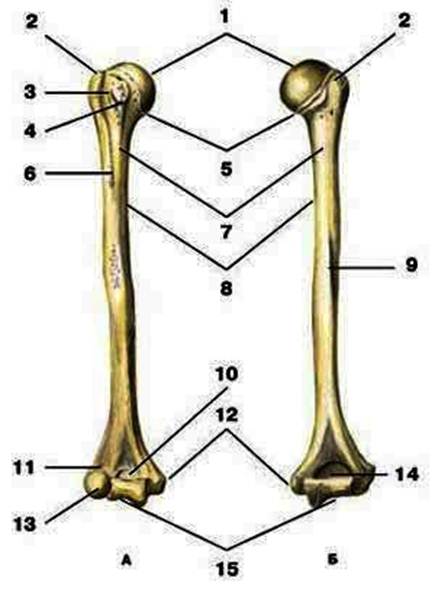

S: Цифра 1 обозначает головка плечевой кости.

S: Число 15 обозначает блок плечевой кости.

S: Цифра 5 указывает на хирургическая шейка плечевой кости.

S: Число 10 обозначает венечная ямка плечевой кости.

S: Число 14 указывает на локтевая ямка плечевой кости.

S: Цифра 9 указывает на борозда лучевого нерва плечевой кости.

S: Число 12 обозначает медиальный надмыщелок плечевой кости.

S: Стрелка указывает на большой бугорок плечевой кости.

S: Стрелка указывает на малый бугорок плечевой кости.